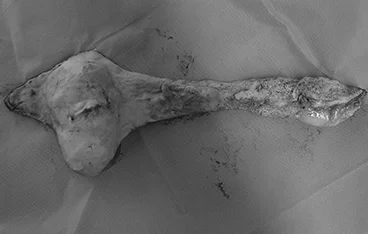

담낭점액종

담낭절제술 + 담관 Flushing

• 담낭절제술